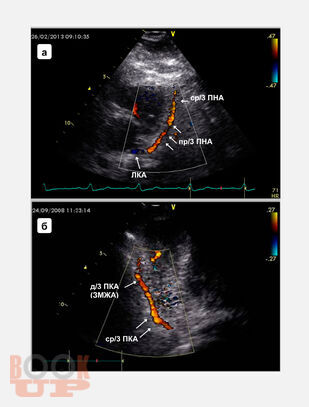

В монографии подробно изложены основные принципы трансторакального ультразвукового исследования магистральных коронарных артерий, включая методические и технические особенности визуализации, обсуждены параметры ламинарного, турбулентного и коллатерального коронарного кровотока, способы оценки и алгоритмы диагностики коронарных стенозов и окклюзий. Также представлены методика определения, способы расчета и критерии оценки резерва коронарного кровотока при трансторакальной допплерографии, показаны диагностическая и прогностическая роли показателя при выявлении гемодинамически значимых коронарных стенозов, окклюзий и определении лечебного эффекта интракоронарных интервенционных вмешательств. Книга рассчитана на кардиологов, врачей функциональной и ультразвуковой диагностики, эндоваскулярных хирургов, патофизиологов, студентов медицинских вузов.